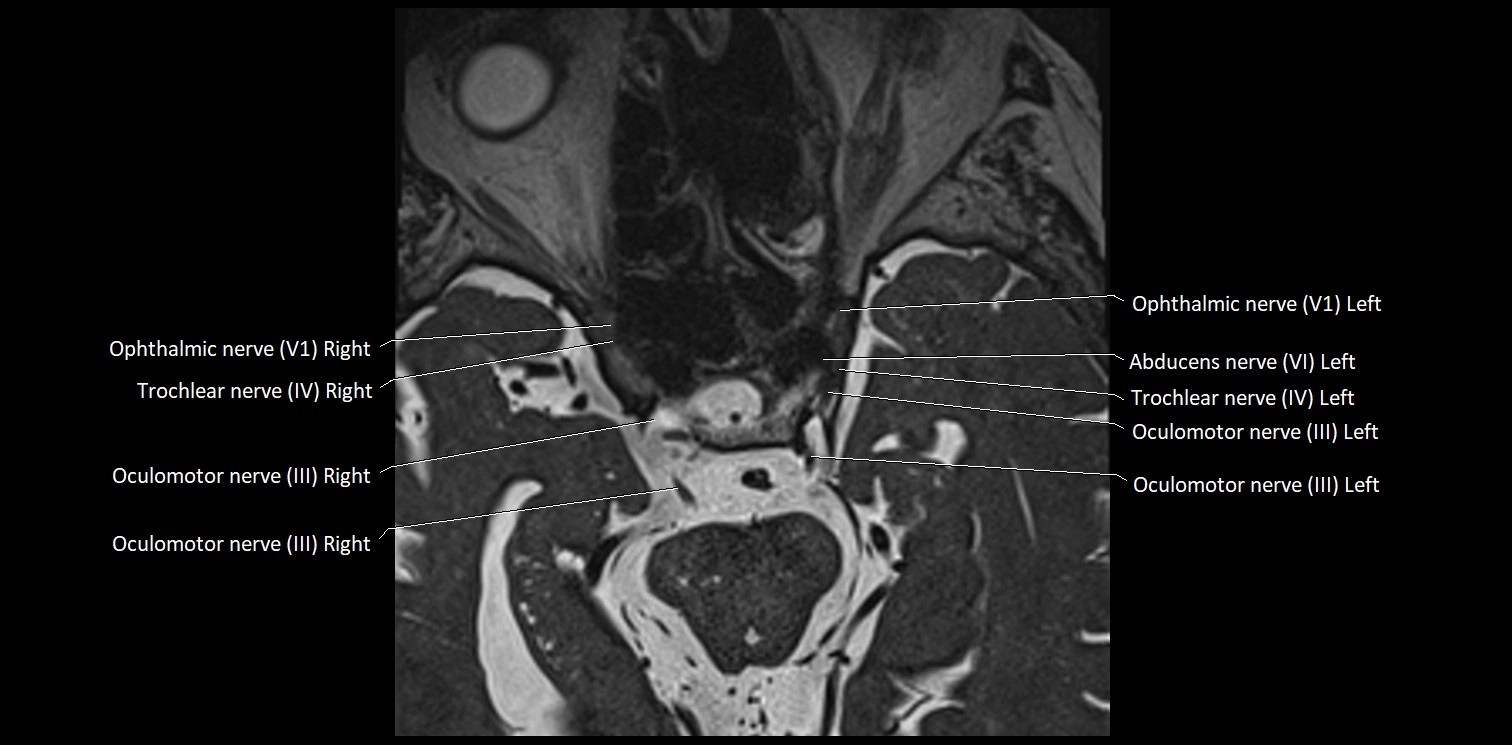

MRI Appearance

• The abducens nerve is a small, thin, linear structure

• Best visualized on high-resolution T2-weighted 3D MRI sequences (e.g., FIESTA or CISS)

• Seen as a hypointense (dark) line running from the brainstem at the pontomedullary junction, traversing the prepontine cistern, and entering Dorello’s canal under the petrosphenoidal ligament, then into the cavernous sinus, and finally the orbit

• May be challenging to visualize in standard MRI due to its small size

• Pathology may be inferred by absence, displacement, or enhancement of the nerve